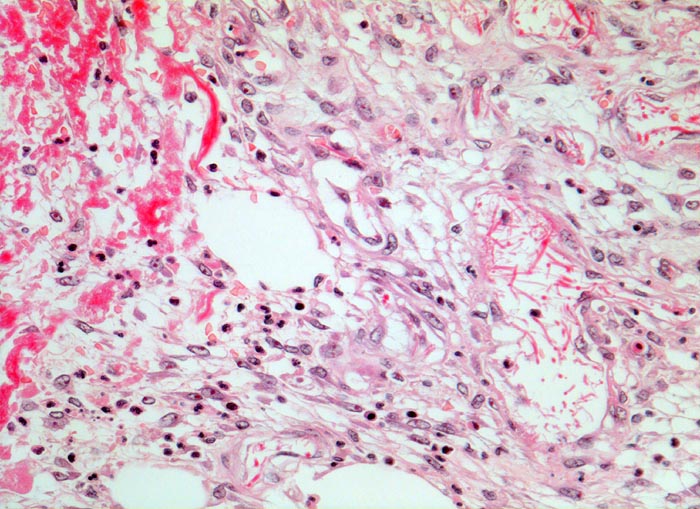

Wundheilung: Granulationsgewebe

Entzündung / Reparatur

Haut, Rumpf

Lockeres, ödematöses Granulationsgewebe mit spindelförmigen Fibroblasten und wenigen neutrophilen Granulozyten. Links im Bild hellrotes Fibrin mit einzelnen neutrophilen Granulozyten.

6 Tage alte Wunde am Abdomen nach Laparotomie.

Histologie

320